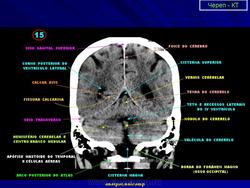

КТ головы в мягкотканном окне.

11.a.slayd105.jpg12.a.slayd106.jpg13.a.slayd107.jpg14.a.slayd108.jpg15.a.slayd109.jpg